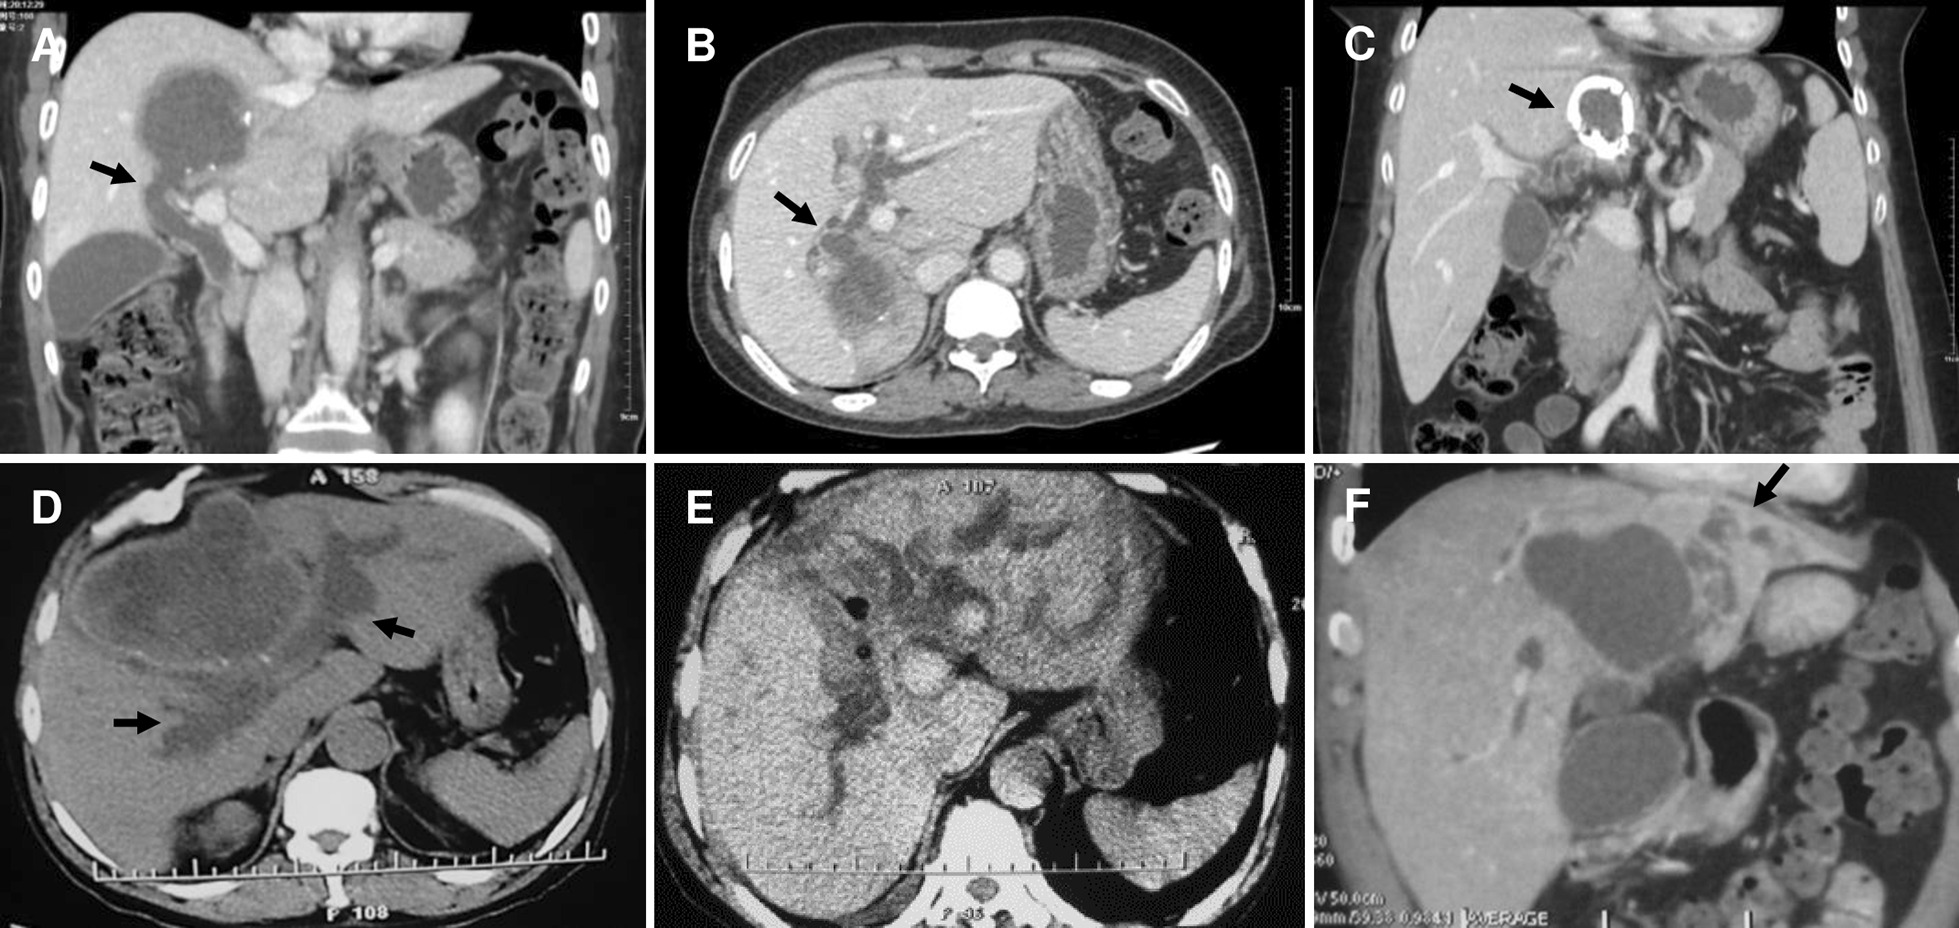

From 2007 March to 2012 December, altogether 660 hepatic CE patients have been hospitalized in our center, and 51 of which (3.5%) without hepatobiliary surgical history underwent PPC in our center due to CE with FCBC. Their most common complaints were abdominal pain, jaundice, nausea and fever. Patient demographics, cyst features and clinical symptoms were presented in Table 1. Preoperative computed tomography (CT) and magnetic resonance imaging and cholangiopancreatography (MR/MRCP) results indicated that, the certain bile duct where the rupture occurred, mostly were perihilar lobular bile ducts (Figs. 1 and 2). PPC was performed in all patients; debris in biliary tracts was removed through CBD using choledochoscopy after cholecystectomy; biliary tract was explored by injecting methylene blue (1:250 dilution with normal saline) to discover the FCBC site (Fig. 3). Owing to the basis of FCBC, setting decompression T-tube and sustaining T-tube drainage have been introduced. Consequently, we retrospectively divided these special subjects into two groups based on their operative procedures (double T-tube drainage group and single T-tube drainage group, specifically mentioned blow), forming this research cohort.